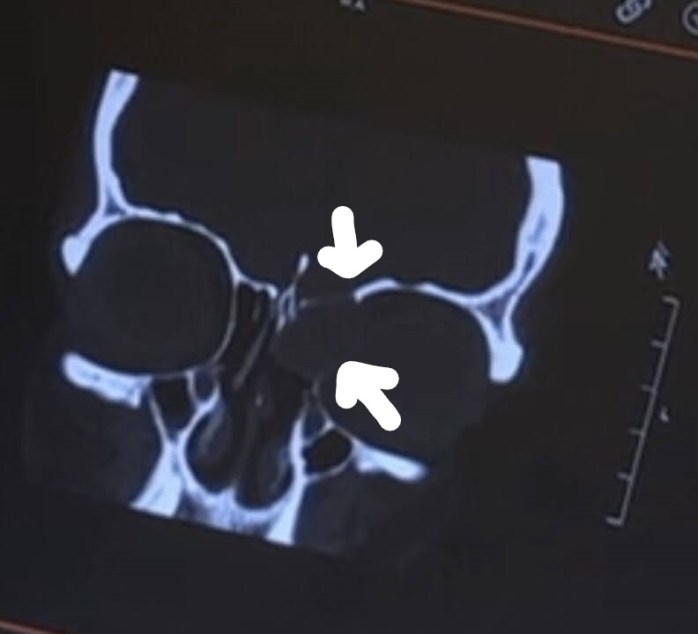

So fast forward to my appointment. I was seeing the head surgeon of Otolaryngology (a head and neck surgeon) at Duke. I saw another Doctor first, I think he was doing his rotation in that area of study, and he as you can imagine asked me a zillion questions as they do at teaching hospitals. I am used to it as I usually go to Duke for my medical needs as I am “high risk” whatever that means. It was not until the Doctor started asking me the same questions, have you had headaches, eye pain, and so on that, I started telling him about what I thought were weird experiences I had that had come to mind over the week between Dr. O’Neil’s questions and this appointment. I recalled several times having what I remembered once telling Chip that I thought I was having a stroke or at the very least Bell’s Palsy. I was out of town at a meeting, and I was at the hotel talking with a co-worker when my left eye began hurting really bad and I began to feel like the left side of my face was drawing up. It was so bad that I wondered if the person I was talking to could see it. I excused myself and when I went to the room I went straight to the mirror. The left side of my face felt like it was pulling on the inside, and my eye was hurting, but it looked fine in the mirror. I honestly thought I was going to have a stroke that night. The next morning this was fine, but it happened a couple more times over the next couple of years. I always tried to figure it out as every time I was talking to someone at an odd angle, and I thought it had something to do with holding my eye in a turned position too long. I always tried to find a logical explanation for things that did not seem right, but I never follow-up on them, and live with it. I have had headaches for so long that I did not even think about them, they were part of my life, and I continuously took over-the-counter pain medication only when it was too bad to tolerate. So, when Dr. O’Neill asked about headaches, I did not think much about it, but over the next week of course I did think about it as well as focused on the headaches, where was it hurting, did it seem any worse, and I shared this information with the doctor. I had complained to my family for months that my face hurt like it felt swollen. I was constantly taking my glasses off because they were pushing against my face, though I am blind as a bat without them and could not leave them off for long. Little things that I had not thought much of were now jumping out at me like I had complained of facial pressure when I bent over. I always thought I had the weirdest issues and would keep pushing on. So, apparently, everything I described to him was what was expected with tumors like this. Wait, what? A tumor? I thought I had an infection. The head surgeon, who is beyond amazing and not bad to look at either, though I am old enough to be his mother I am sure, showed me the CT scan, and apparently, these things had deteriorated the bone of my left eye orbit and at the base of my brain on the left as well.

This arrow is pointing to the mass and where it had eroded my eye socket